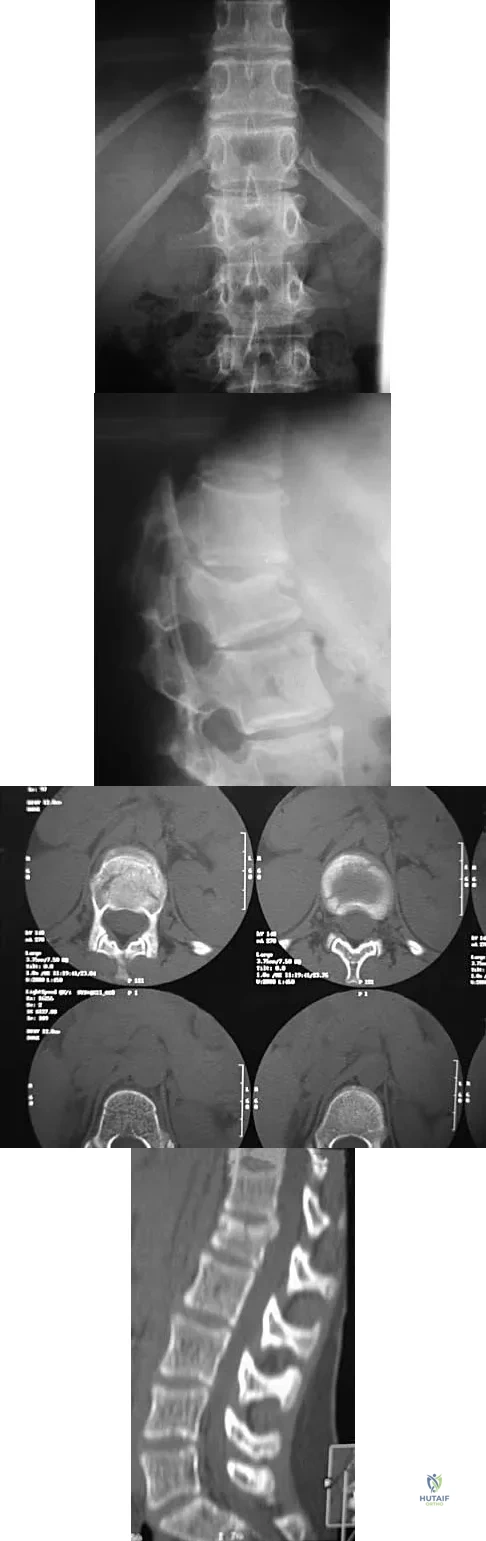

A patient underwent an anterior cervical diskectomy and interbody fusion for a C5-6 herniated nucleus pulposus and left C6 radiculopathy 8 months ago. He now reports new onset of severe neck pain and left C6 radicular pain, with wrist extension weakness. The radiograph and CT scan shown in Figures 26a and 26b reveal pseudarthrosis at C5-6. The next step in management should consist of

Brodsky and associates reviewed 34 cases of cervical pseudarthrosis after anterior fusion. Seventeen were treated with revision anterior fusion and 17 with posterior foraminotomy and fusion. Good results were seen in 75% of patients who underwent revision anterior surgery, but better results (94%) were seen with posterior surgery, including foraminotomy and stabilization. Tribus and associates reported treatment of 16 patients with pseudarthrosis using revision anterior debridement of the fibrous tissue and fusion with autograft and plates. There was improvement of the neck in 75% of the patients, nonunion in 19%, continued weakness in 28%, and dysphagia in 5%. Farey and associates reported on 19 patients treated with posterior foraminotomy, stabilization, and fusion with a fusion rate of 100%, resolution of arm pain in 94%, resolution of weakness in 100%, and resolution of neck pain in 75%. It would appear that posterior foraminotomy is more effective for relieving arm pain and neurologic deficits associated with pseudarthrosis. Posterior fusion has the most reliable rate of arthrodesis in this setting. Dysphagia is reported in some patients undergoing more extensive anterior dissections required for applying plates. A neck brace is unlikely to aid in healing of pseudarthrosis in a patient who underwent surgery 8 months ago. A neck brace would be most effective within the first 3 months if a delayed union is identified. Brodsky AE, Khalil MA, Sassard WR, Neuman BP: Repair of symptomatic pseudarthrosis of anterior cervical fusion: Posterior versus anterior repair. Spine 1992;17:1137-1143. Tribus CB, Corteen DP, Zdeblick TA: The efficacy of anterior cervical plating in the management of symptomatic pseudarthrosis of the cervical spine. Spine 1999;24:860-864.